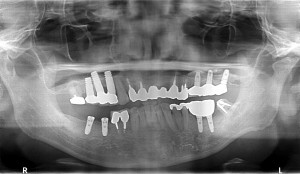

50歳代男性

上顎が何本か残っておられましたが全て動揺があり、抜歯が適当かと思われましたので、抜歯させて頂き、

総入れ歯を当院にて装着させて頂いた人でした。

抜歯後、4か月程経過しましたので、スイス製ストローマンインプラントRNを7本埋入させて頂きました。

左上顎洞底は薄かったため、ソケットリフトを併用させて頂きました。

5カ月後ぐらいに最終補綴物を装着する予定です。

術前

術後